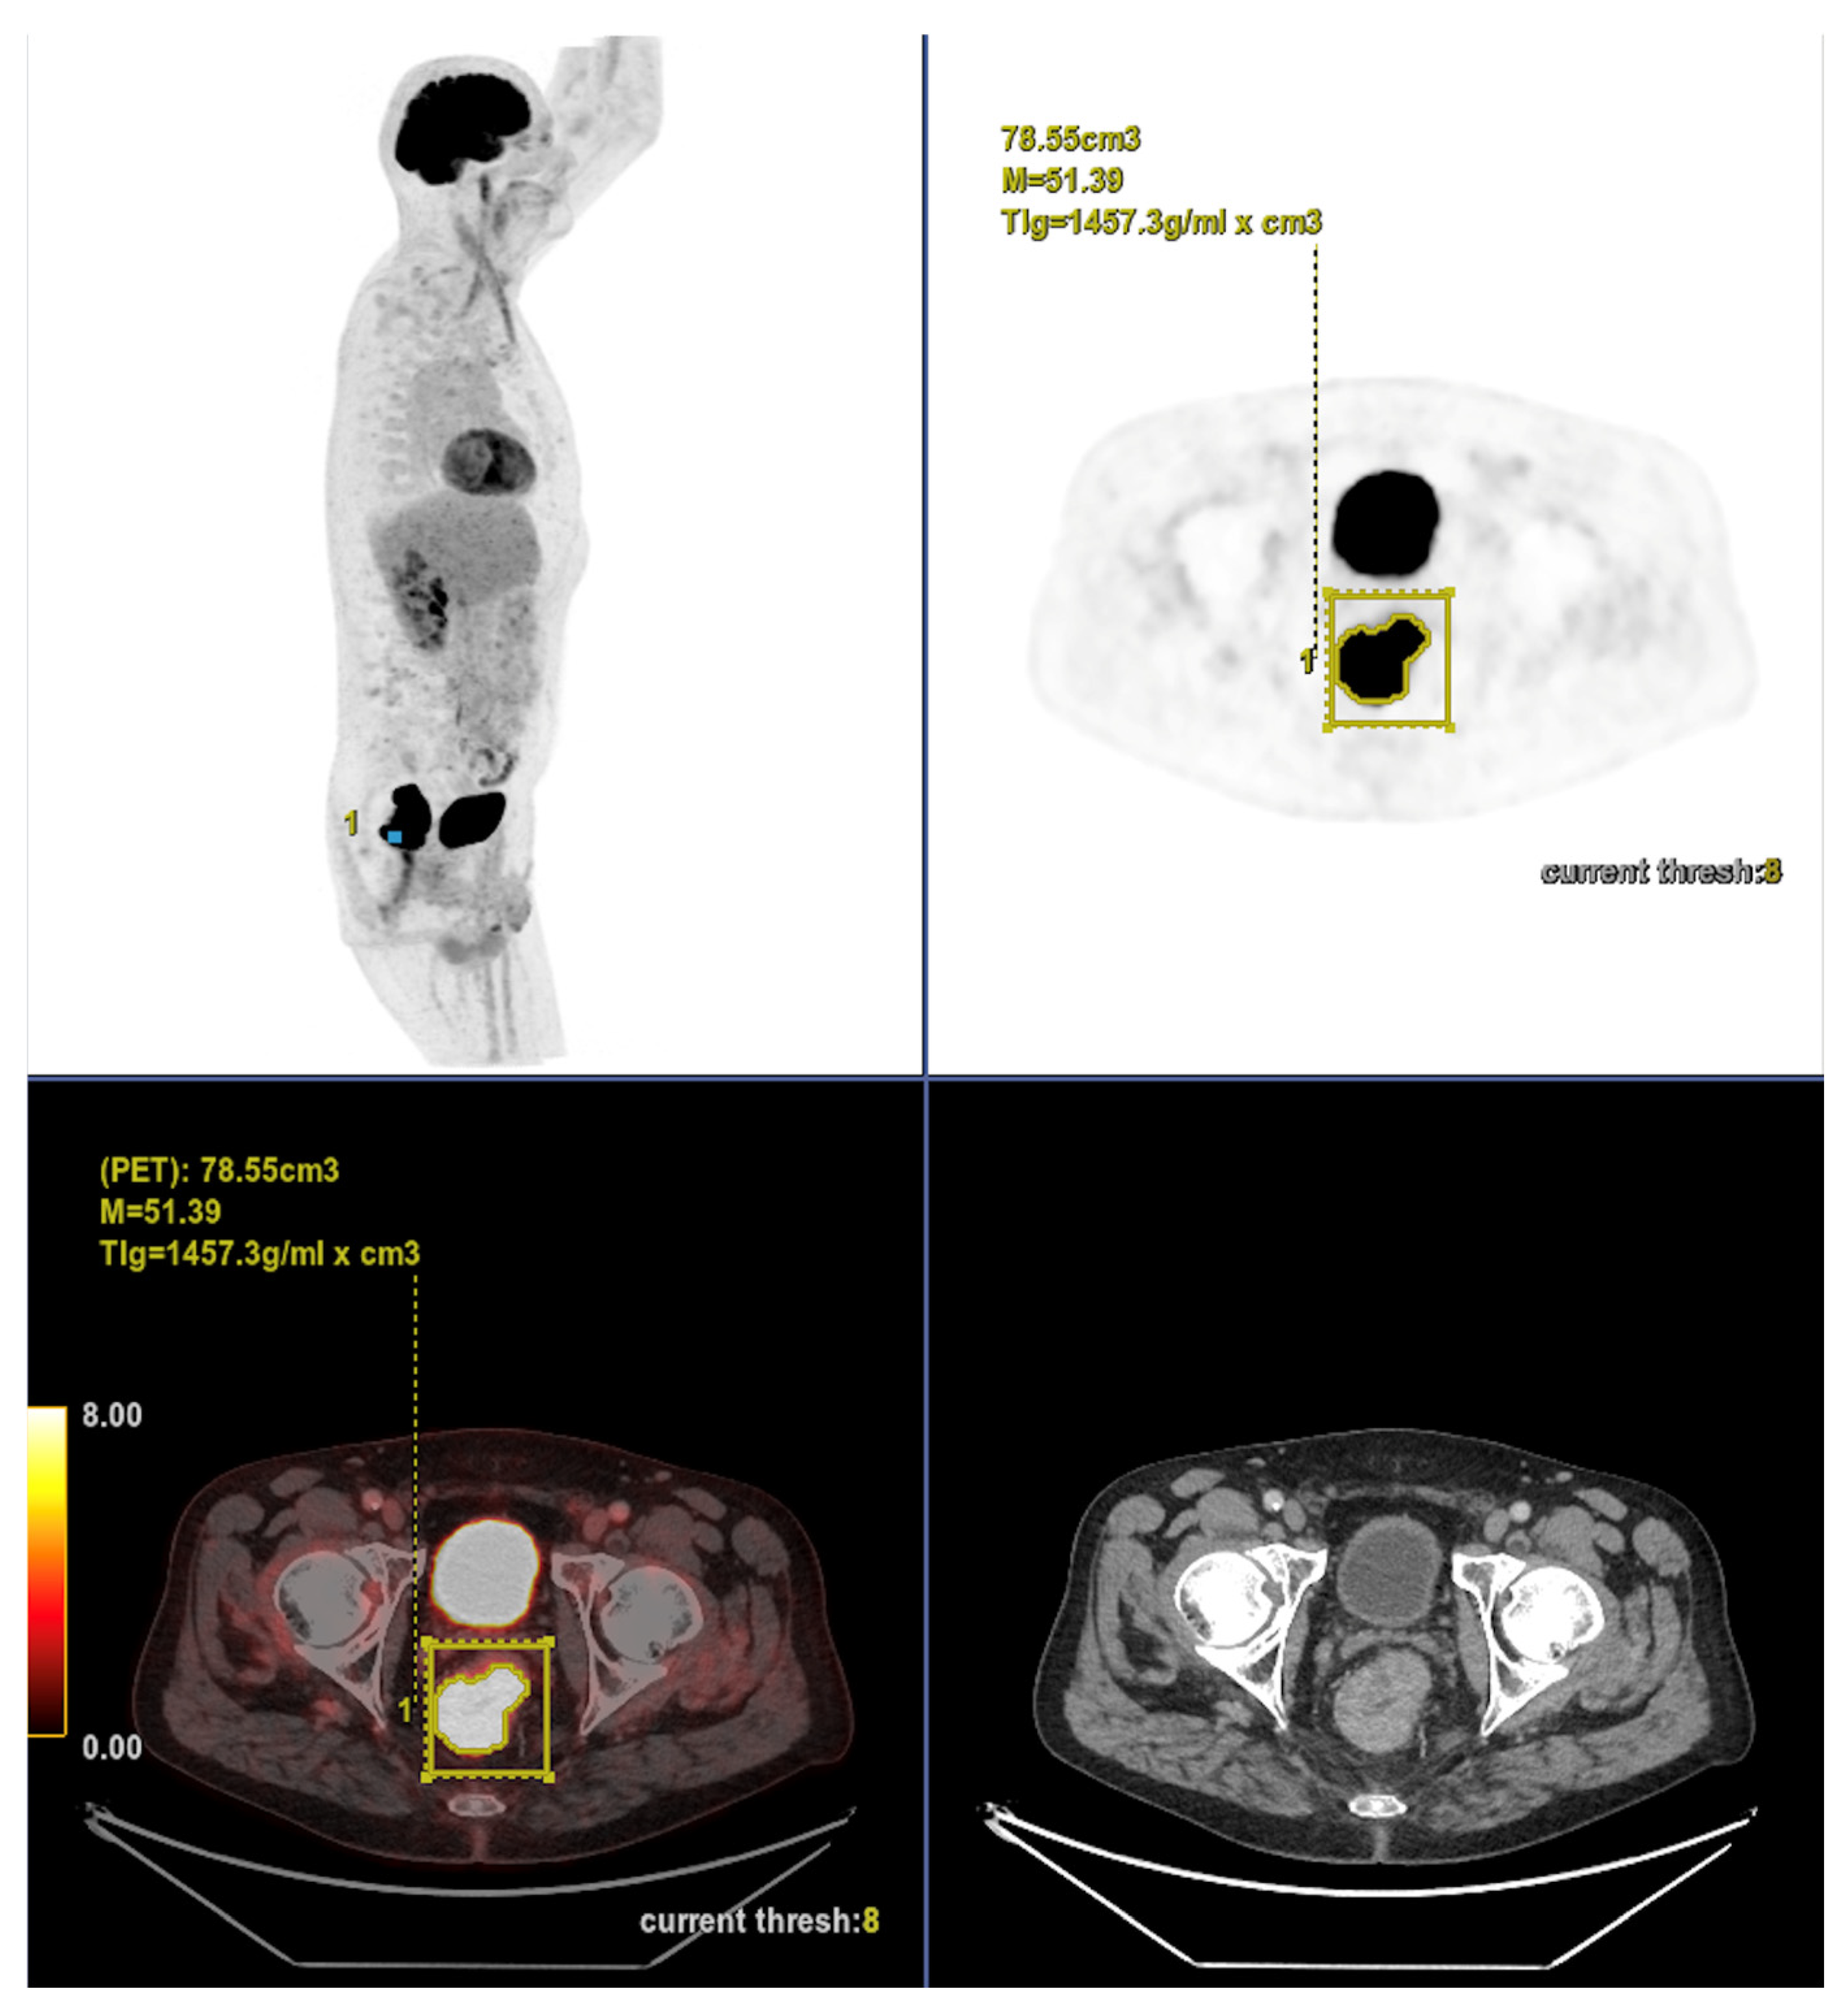

Altogether, these analyses demonstrate that MTV of the primary tumor is a consistent predictor of both OS and PFS. While OS was primarily influenced by sex and MTV, PFS was more strongly determined by UICC stage and MTV, as displayed in Figure 6. For a clearer understanding of the presented results, Figure 7 shows a representative example of manual delineation of the primary tumor on baseline FDG PET/CT.

Figure 7.

Representative example of manual delineation of a primary rectal tumor on baseline FDG PET/CT showing manual delineation of the metabolically active tumor volume (first row) on the PET image with corresponding fused PET/CT image and CT image with iodinated contrast medium (second row). Morphological features, including tumor shape (circular or semi-circular), cranio-caudal extension (in cm), and overall tumor volume (in cm3), were assessed on the CT image (often with contrast medium) coregistered with the PET images. Tumor shape was determined on the axial plane, cranio-caudal extension on the sagittal plane, and tumor volume after careful delineation on all planes. Iodinated contrast medium was administrated in 70% of cases after exclusion of contraindications. Metabolic parameters, including SUVmax, SUVmean, MTV and TLG, were systematically extracted from the segmented tumor (yellow in this figure). SUVmax (M in this figure) and TLG were automatically displayed. SUVmean could be obtained by simply replacing SUVmax with SUVmean in the parameter selection. MTV was automatically calculated from TLG and SUVmean values displayed on the workstation. The highlighted region in yellow represents the 3D contour of the primary tumor, excluding physiological uptake and non-tumor regions.

Case 1: An 80-year-old patient with stage IVA rectal cancer and synchronous anal carcinoma, presenting with a large circumferential primary tumor showing a craniocaudal extension well above the predictive cut-off (13.0 cm vs. 6.2 cm; volume: 79.2 mL) and a metabolic tumor volume markedly exceeding both prognostic thresholds (MTV 79.0 vs. 35.49 for OS and 32.08 for PFS). Baseline FDG PET/CT demonstrates locoregional nodal involvement and a solitary liver metastasis in segment VII. The patient experienced rapid disease progression, with a progression-free survival of 8 months and an overall survival of 27 months.